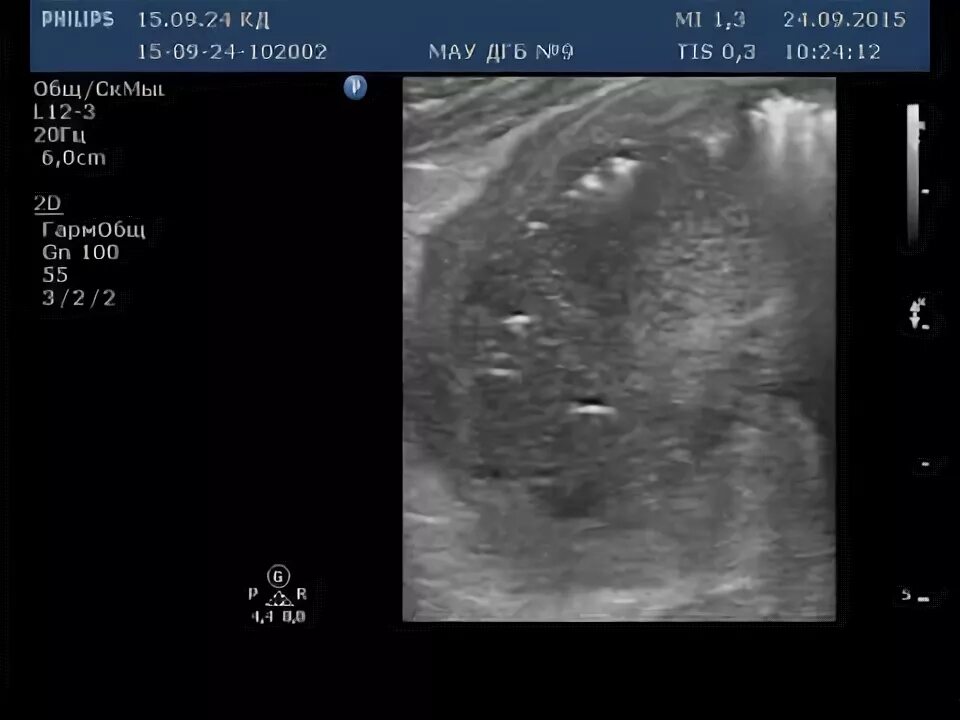

Какое узи при аппендиците